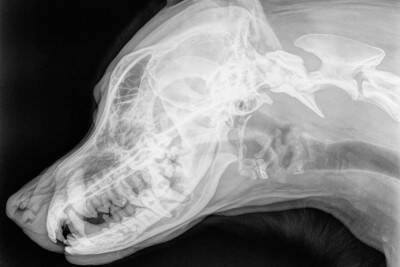

しかし、犬はそのような体の仕組みにはなっていないため、抱っこしている高さから落としたときに、頭や背中を打ちつけてしまうことがあります。尻尾側よりも頭側の方が重いため、頭から落ちて、衝撃が頭や首に集中してしまう危険性もあるのです。

そのため、犬が落下したときに頭を打つと、脳震盪などを起こすことが考えられます。落ちた直後に立ち上がることができなかったり、立ち上がっても目の焦点が合っておらずふらふらと歩いていたりする場合は危険です。

一時的な衝撃を受けただけですぐに回復することもありますが、そうした状態が続く場合や、その後嘔吐をくり返したり体が痙攣したりした場合は、すぐに動物病院に連絡してください。

最悪の場合、脳挫傷や脳出血といった重篤な症状を引き起こしている可能性もあるので、むやみに体を動かす前に、一度電話で獣医師の指示を仰ぐと安心です。